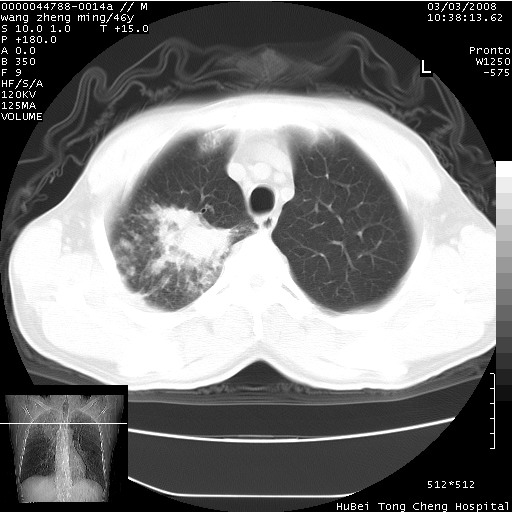

以下是引用卜一在2008-3-22 1:37:00的发言:[br]右肺实质性肿块,边缘不整,明显见毛刺征 分叶征及胸膜凹陷征,右上叶支气管明显变窄,远端散在的片状 斑片状实变影。另:左肺门较大肿块,支气管受累 变窄,远侧见阻塞性肺炎。纵隔内见肿大淋巴结。多考虑:右肺周围性肺癌伴左肺门 纵隔淋巴结转移!